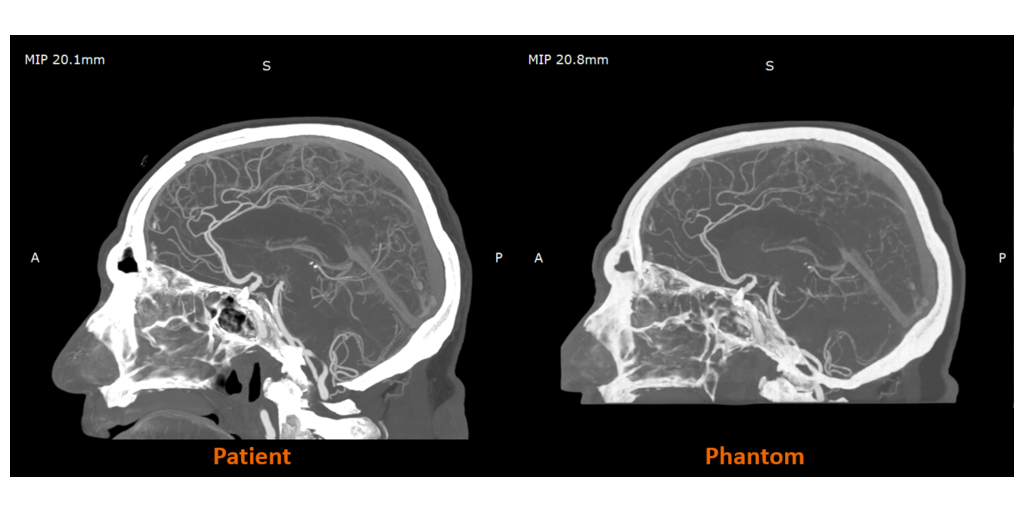

RadioMatrix is the first and only 3D printing material that enables precise control of radiopacity - allowing users to produce patient-specific models with repeatable, consistent, and fully tunable visibility on X-ray based imaging. Stratasys developed RadioMatrix to support a new era of medical imaging. Its unmatched fidelity for computed tomography (CT) phantoms was later underscored by research conducted with Siemens Healthineers, which validated RadioMatrix’s capabilities and accuracy for accelerating innovation in device testing, calibration, and education.

UK-based work with partners such as CPI and Beaumont Hospital is already demonstrating the impact of radiopaque 3D-printed models in practice, with radio-realistic cerebral angiography phantoms being used to improve the fidelity of imaging-based training and create more controlled, repeatable environments for research.

Early research from the Stratasys–Siemens Healthineers collaboration shows that 3D printed RadioMatrix™ phantoms can closely replicate real human tissue in CT imaging, with deviations reported as low as single Hounsfield units (HU) in critical areas such as grey matter and veins. By combining Stratasys’ Digital Anatomy™ 3D printing technology and radiopaque materials with advanced imaging algorithms, the partners are demonstrating anatomically realistic, radio-accurate phantoms that preserve fine anatomical details and pathological variations while offering a more consistent, ethical alternative to cadavers. These models are expected to improve how radiologists validate and optimize CT protocols and accelerate the development of new imaging algorithms for more precise diagnosis and treatment planning.